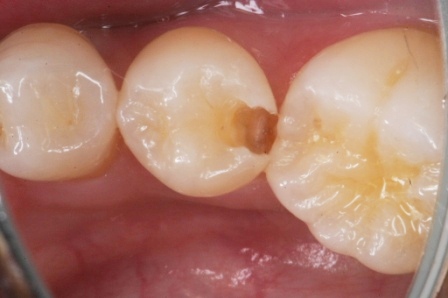

下顎7番の頬側歯茎部カリエスの原因 2025.06.04